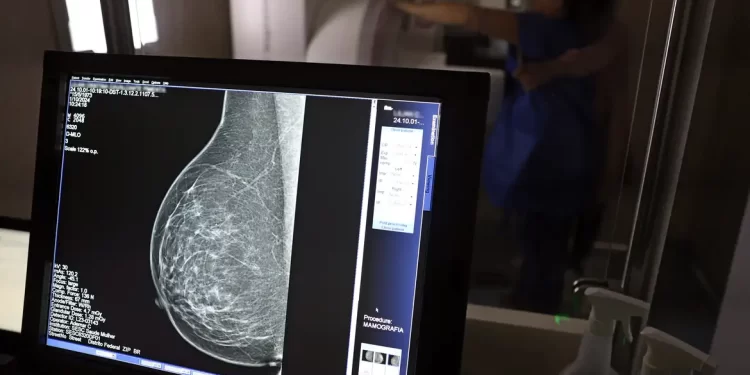

O Ministério da Saúde passou a recomendar o acesso a mamografia, via Sistema Único de Saúde (SUS), para mulheres de 40 a 49 anos – mesmo que não haja sinais ou sintomas de câncer de mama. De acordo com a pasta, a faixa etária concentra 23% dos casos da doença, e a detecção precoce aumenta as chances de cura.

Até então, a orientação era que o exame fosse feito a partir dos 50 anos.

A medida faz parte de um conjunto de ações anunciadas nesta terça-feira (23) voltado para a melhoria do diagnóstico e da assistência. A recomendação para mulheres a partir dos 40 anos é que o exame seja feito sob demanda, em decisão conjunta com o profissional de saúde.

As mamografias via SUS em pacientes com menos de 50 anos, de acordo com a pasta, representam 30% do total, o equivalente a mais de 1 milhão apenas no ano de 2024.

Outra medida anunciada é a ampliação da faixa etária para o rastreamento ativo – quando a mamografia é solicitada de forma preventiva a cada dois anos. A idade limite, até então, era 69 anos. Agora, passa a ser 74 anos. Dados do ministério revelam que quase 60% dos casos de câncer de mama estão concentrados entre 50 e 74 anos.

“A ampliação do acesso à mamografia aproxima o Brasil de práticas internacionais, como as adotadas na Austrália, e reforça o compromisso em garantir diagnóstico precoce e cuidado integral às mulheres brasileiras. O câncer de mama é o mais comum e o que mais mata mulheres, com 37 mil casos por ano”, reforçou a pasta.

Os números mostram que, em 2024, cerca de 4 milhões de mamografias para rastreamento e 376,7 mil exames diagnósticos foram realizados no SUS.